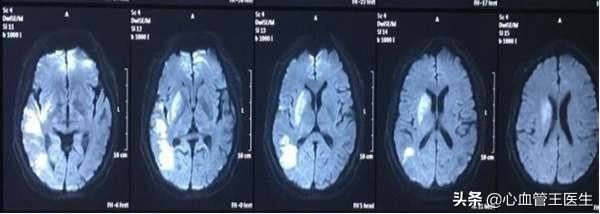

脳血管の狭窄は通常脳虚血で現れ、脳血管の閉塞は頸動脈プラークと直接関係しているため、頸動脈超音波検査で頸動脈の狭窄とプラークを判定することで、最初に脳血管の状態を把握し、その結果によって薬物治療の可否を決めることができる。脳血管が閉塞すると脳梗塞となり、片麻痺、失語症、片麻痺などの症状が現れます。